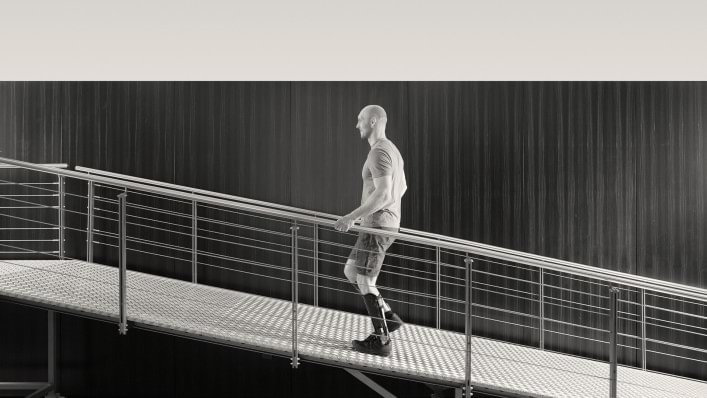

Vielen Menschen leiden unter einer Fehlhaltung oder Fehlfunktion/Lähmung des Bewegungsapparates, entweder von Geburt an, erworben, wie zum Beispiel durch einen Unfall oder als Folge einer neurologischen oder orthopädischen Erkrankung.

Eine Orthese ist ein medizinisches Hilfsmittel, das dem Funktionsausgleich, der Ruhigstellung, Führung oder der Stabilisierung von Gliedmaßen oder des Rumpfes dient. Es können hiermit zum Beispiel Gelenkschmerzen reduziert und die Qualität des Gehens und Stehens verbessert oder auch erst ermöglicht werden.